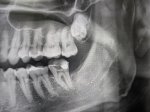

Я каждый день чистил зубы. И знаете,где у меня образовался кариес? Наверху справа в пространстве меж — Я каждый день чистил зубы. И знаете,где у меня образовался кариес? Наверху справа в пространстве между шестеркой и семёркой, куда щетинки зубной щётки не достают. Вот прямо там, в этой узенькой промежности блять развился пришеечный кариес. Теперь он адски болит когда я пытаюсь есть и кровоточит. Блять, хочется уже просто сдаться нахуй. Я и ирригатором пользуюсь и дорогой пастой рокс зубы чищу по несколько раз в день и всё равно блять эта хуйня. Я что блять, должен был ещё зубной нитью пользоваться?? Никто блять не пользуется зубной нитью, спросите у любого. Тем более как я нить так глубоко в рот засуну до седьмого зуба Опять идти к зубным палачам и отдавать им деньги Вы не задумывались, какой это вообще бред, что зубы разрушаются?? Представьте блять, что если вы не принимаете душ, то у вас кожа начинает гнить и разлагаться, образуются нарывы и кисты, и душ становится способом выживания и сохранения здоровья, а не просто гигиеной. Такой же бред с зубами блять, ой ой смотрите я выдерживаю давление в 100кг, но умираю от углеводов. Эволюция всех гнилозубиков ещё миллионы лет назад должна была выкосить.